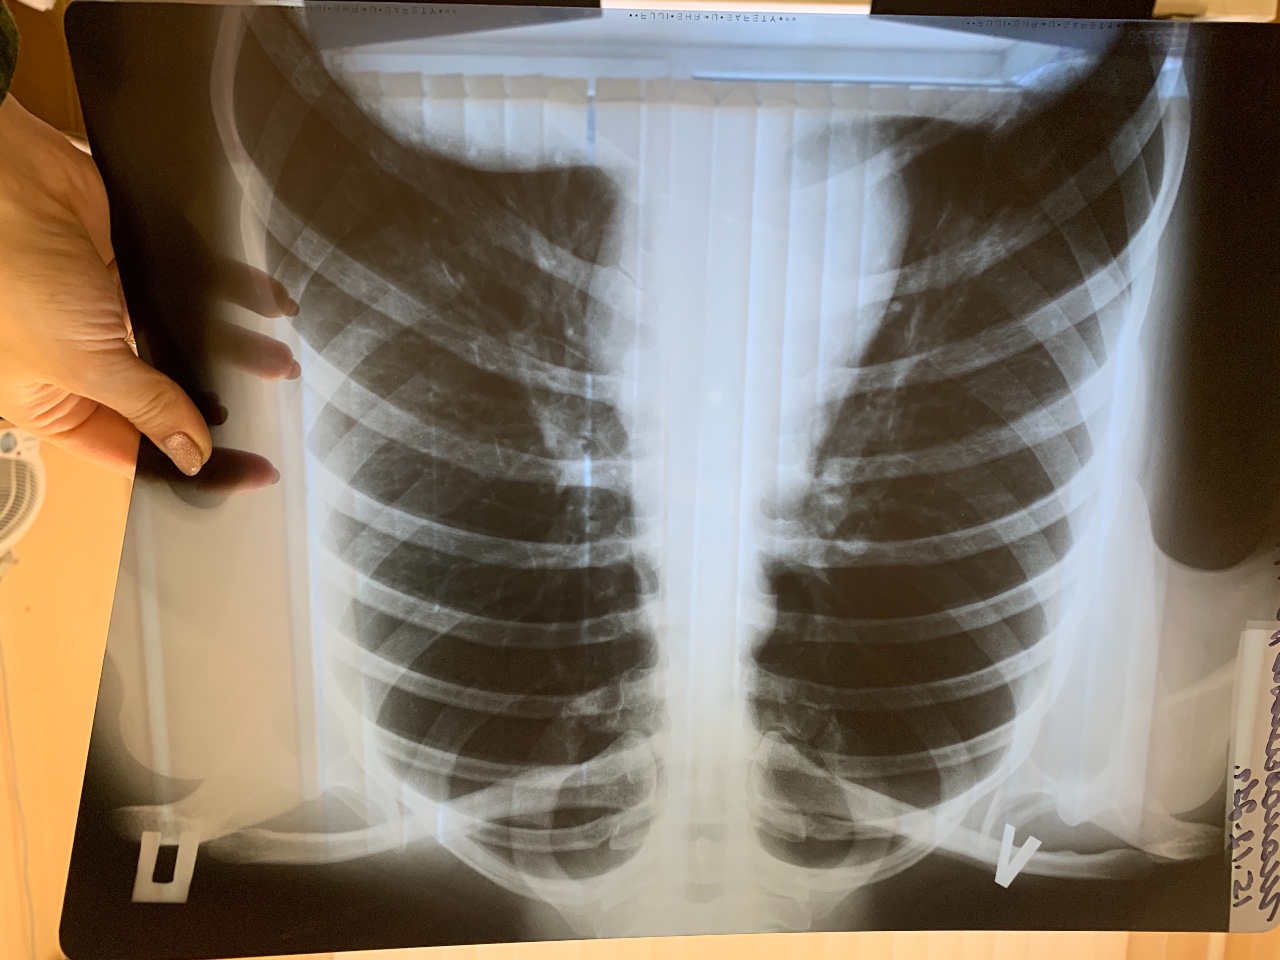

Что такое малоконтрастная рентгенограмма органов грудной клетки